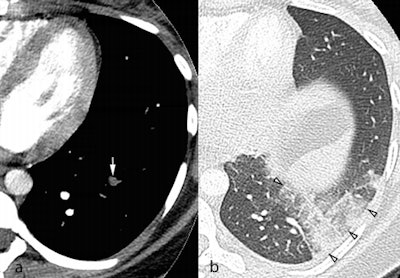

Axial CTPA images in the soft tissue (a) and lung windows (b) from a 25-year-old pregnant woman presenting with acute chest pain. A segmental pulmonary embolus was detected in the left lower lobe (a, white arrow), with associated triangular-shaped areas of subpleural alveolar density (b, arrowheads), consistent with pulmonary infarction. Image courtesy of Dr. David Rotzinger and European Radiology.Rotzinger and Schmidt said they decided to look at this topic because they noticed that in the past few years of daily work in their emergency department, more and more women entered with suspected PE, nearly always with a negative result. This piqued their interest in determining the exact results. In addition, CT is undergoing rapid technological change, leading to a reduction of radiation dose and section thickness. Would that influence image quality?